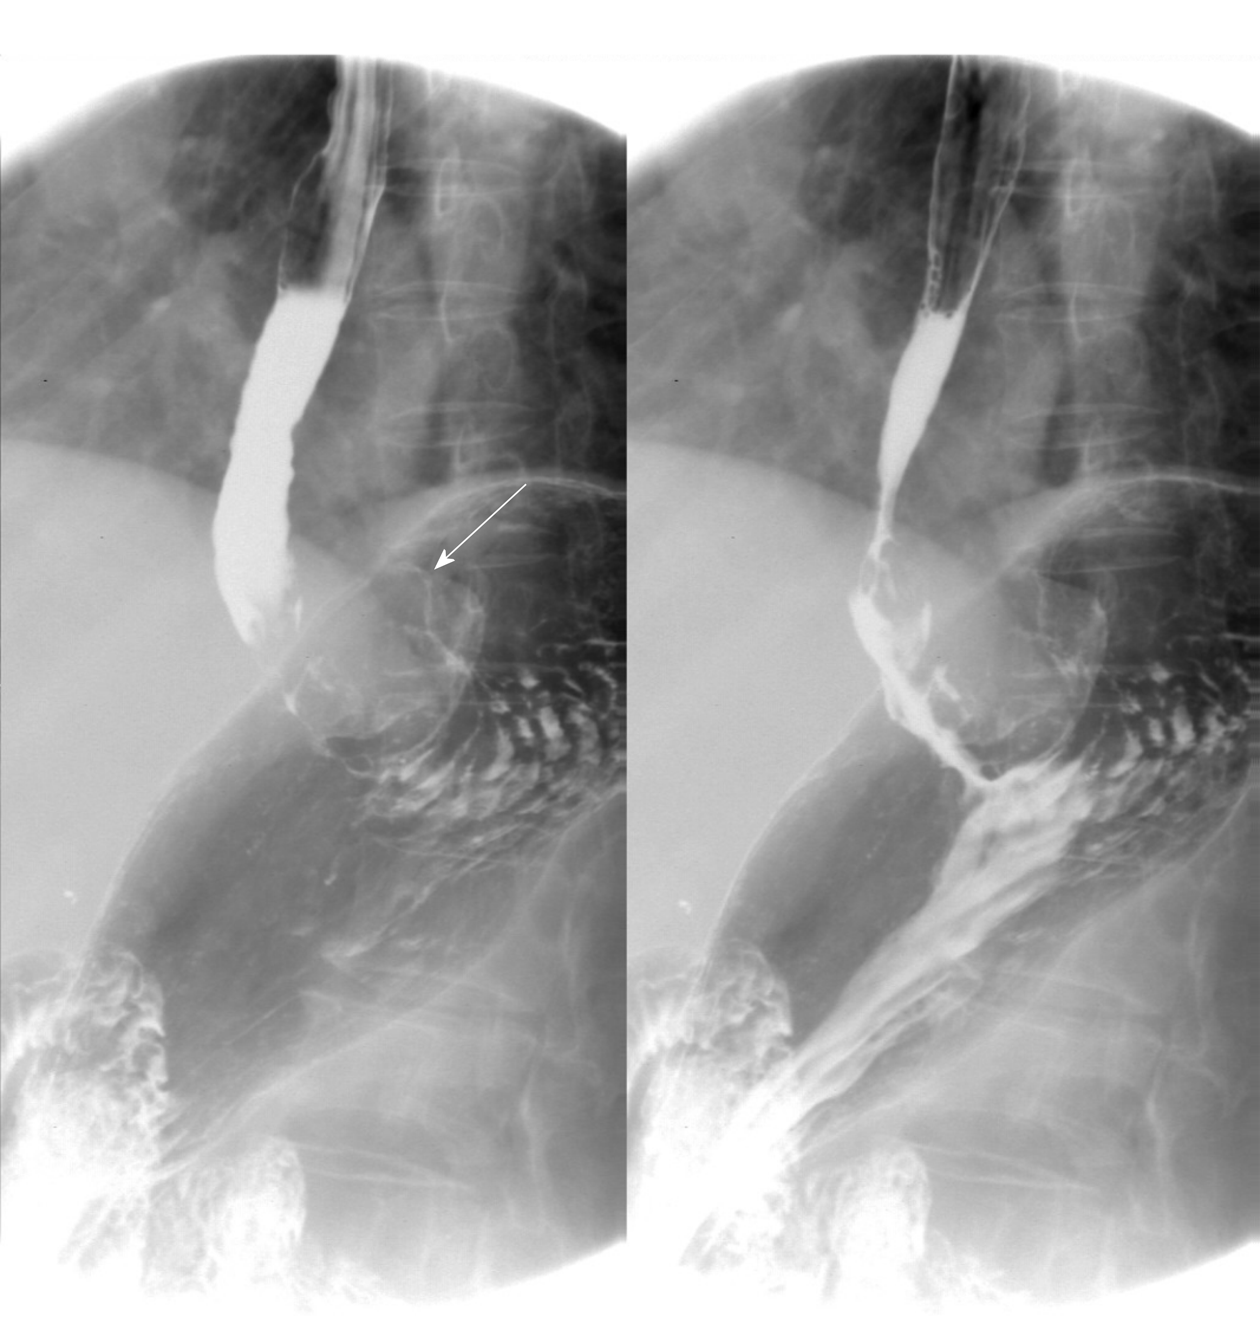

Gastric cardia radiology. Diagnostic centers of america dca is a leading diagnostic imaging facility offering a full array of imaging services in palm beach county florida. We have five state of the art radiology imaging centers in boca raton boynton beach delray beach and wellington florida. The gastric cardia is characterized on barium stud ies by three or four stellate folds that radiate to a central point at the gastro esophageal junction also known as the cardiac rosette fig 2 12. Variations and benign influences may closely resemble the more dangerous lesion.

Thick tortuous folds or lobulated filling defects in the cardia or fundus. Right gastroepiploic artery inferiorly and left gastroepiploic artery and short gastric arteries superiorly fundus of the stomach. Results of surgical treatment of carcinoma of the esophagus and gastric cardia. The collection of cases presented here comprises only that material which is rare in our experience or quite new to us.

Epidemiology gastric diverticula are rare and c. Weight loss surgery is about reducing your weight and gaining good health. Gastric diverticula are sac like projections that usually originate from the gastric fundus most commonly on the posterior surface. They are the least common of the gastrointestinal diverticula.